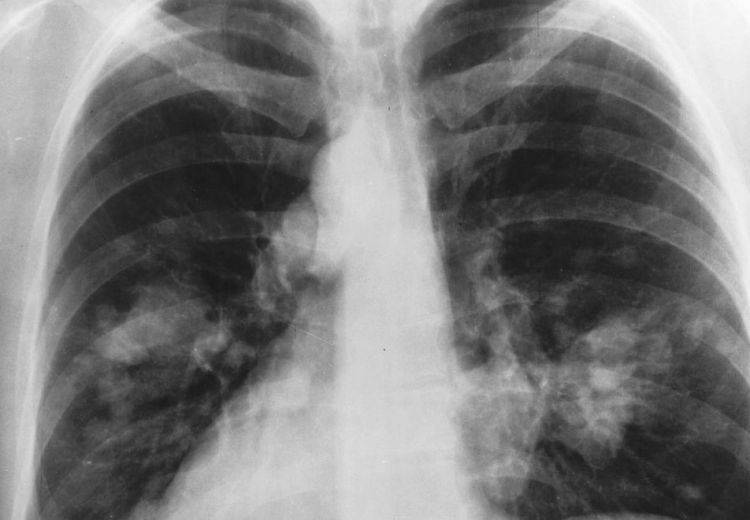

Image (top): An example of an X-ray of the chest, courtesy of National Institutes of Health-National Cancer Institute. (public domain)